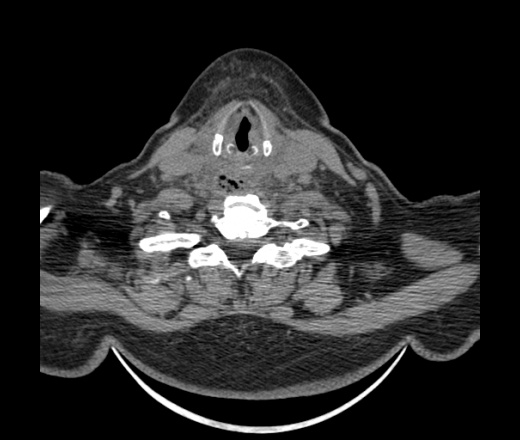

Женщина поступила в х/о спустя 4 дня после того как при употреблении карася подавилась костью.

Наличие газа в средостении на протяжении тел С2-С6 (медиастинальна эмфизема); рыбная кость на уровне тела С6.

При всем уважении, но говорить о медиастинальной эмфиземе, оценивая мягкие ткани шеи, как-то слишком резко. На мой взгляд, это ретрофарингеальное пространство.

Эвакуировали почти 100мл гноя. Но кость не смогли найти. Думаю что она даст дальнейшее ослоднение. Эндоскопически за черпалонадгортаной звязкой не смогли зайти в пищевод, все мягкие ткани отечные, просвет пищевода сдавлен. По всей видимости параэзофагеальная клетчака тоже задействована. Эмпиема, если ее можно так назвать, незнаю как правильно дошла до уровня яремной вырезки. Чем закончиться напишу. Ждем медиастинита.

Согласен с Вами; конечно, наличие газа в клетчатке ретрофарингеального пространства (затмение с опечаткой..). К сожалению, процесс "продвигается" к медиастиниту. Но почему никто, не отмечает наличие рыб. кости; или это для Всех очевидно?

Кость то мы сразу выявили, размеры где то 17*2мм, но ее так и не получается найти в этой каше